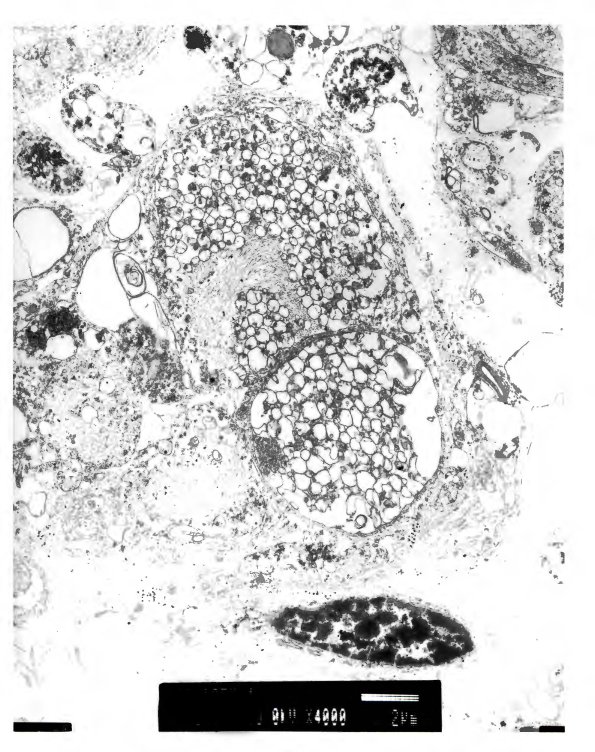

These vesicle rich swellings likely correspond to the non-argyrophilic swellings shown in 2A15-19. (electron micrographs)